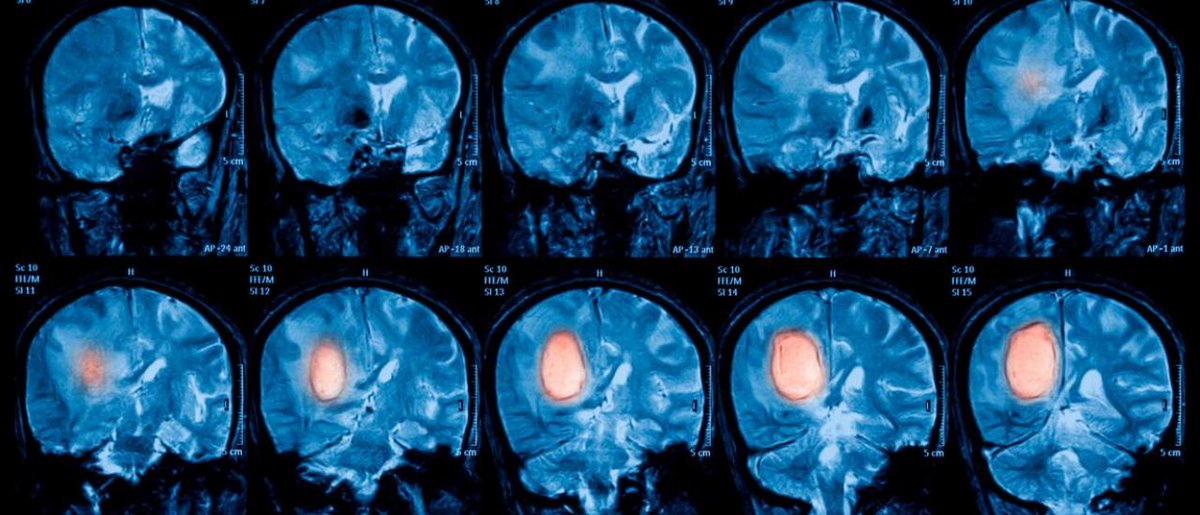

Что значит неоперабельная опухоль

Что значит неоперабельная опухоль 109 фотографий